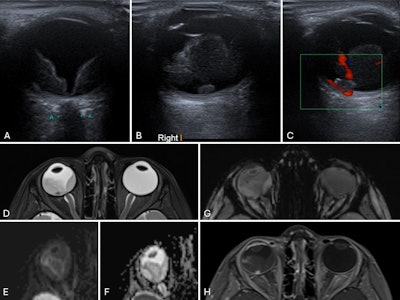

Coats disease in a 3-year-old child. (A) Axial ultrasound of the right eye shows retinal detachment with echogenic subretinal fluid. (B) A small ovoid nodule is seen adjacent to the retina, demonstrating homogeneous echogenicity. (C) Color Doppler imaging shows no internal vascularity within the nodule. (D) Axial T2-weighted MR image of the orbits reveals a slightly small right globe with retinal detachment and subretinal fluid of intermediate signal intensity. The previously identified nodule, located in the foveal region, appears hypointense. (E–F) No evidence of restricted diffusion. (G) Susceptibility-weighted imaging shows no appreciable blooming artifacts to suggest calcification. (H) The lesion demonstrates avid enhancement on post-contrast images. Overall findings are consistent with Coats disease with an enhancing subfoveal nodule.